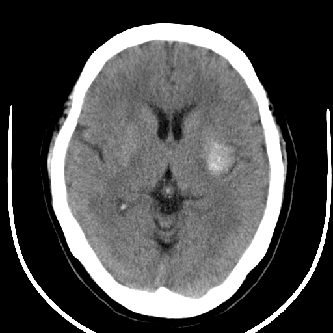

标题: CT4588:是出血吗?

44 f,平时头晕,有高血压病史,近日加重。其它检查无异常。

尽管密度类似于出血,但其密度明显不均匀,中间有多枚小点状致密影似钙化。同时,病灶周围没有水肿,没有占位效应,临床又没有其他症状。

首先考虑动静脉畸形,建议增强。

左侧豆状核后部不均匀高密度影,中间有斑点状钙化灶,周围无水肿及占位效应,考虑血管瘤。

病人做了mr,诊断为:海绵状血管瘤.